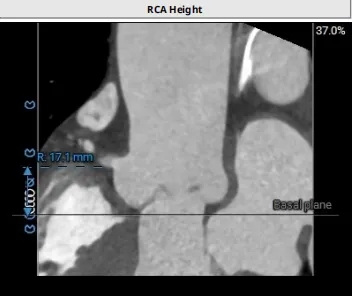

冠脉风险评估

Right Coronary 17.1mm

左冠开口较低,,结合瓦氏窦大小,预估冠脉风险相对较低